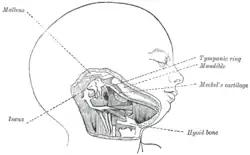

Embryologically, the malleus is derived from the first pharyngeal arch along with the incus.[3] In humans it grows from Meckel's cartilage.[3]

Head and neck of a human embryo eighteen weeks old, with Meckel's cartilage and hyoid bone exposed.